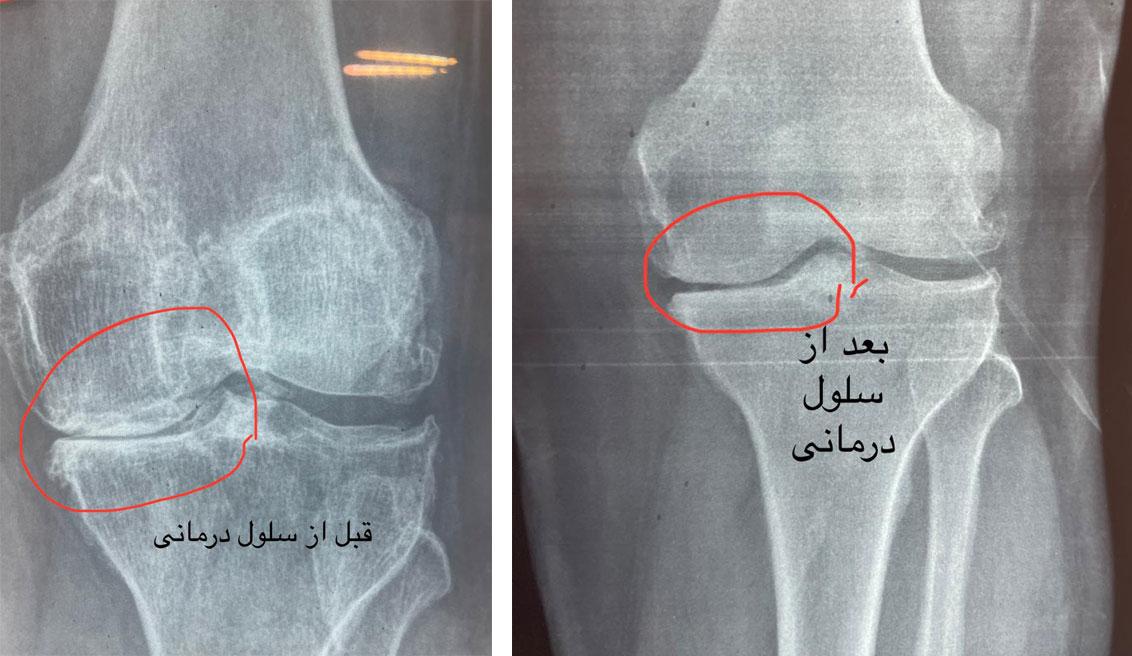

تکنولوژیهای درمانی نوینی مانند سلولدرمانی با بهرهگیری از سلولهای بنیادی، چشماندازهای جدیدی برای بازسازی آسیبهای مفصل زانو به وجود آوردهاند.

در این روش، سلولهای بنیادی، که از منابعی چون مغز استخوان یا بافت چربی بیمار استخراج شدهاند، جدا و تکثیر میشوند. سپس این سلولها به داخل مفصل زانو تزریق میشوند.

این سلولهای بنیادی دارای توانایی ترمیم بافتهای آسیبدیده مفصل، از جمله غضروف، رباط و منیسک هستند. علاوه بر این، آنها به کاهش التهاب، احیای سلولهای مفصلی، و در نهایت بهبود عملکرد مفصل منجر میشوند.

مطالعات نشان دادهاند که سلولدرمانی میتواند به بهبود درد مفصل، افزایش دامنه حرکتی، و بهبود کیفیت زندگی بیماران مبتلا به آرتریت و آسیبهای مفصل زانو کمک موثری نماید.

ولی جدیدترین روشی که امروزه در تمام دنیا برای درمان ارتروز و ساییدگی زانو و ستون فقرات استفاده میشود تزریق مستقیم سلولهای بنیادی داخل زانو یا ستون فقرات یا همان سلول درمانی است . مزیت سلول درمانی نسبت به روشهای پیشین از جمله تزریق ازن یا پی آر پی اینست که این روشها بیشتر برای مفصل حالت تسکین ایجاد میکنند و در واقع مسکن هستند در حالیکه سلول درمانی منجر به تشکیل غضروف در مفصل شده و از طریق ایجاد غضروف درد را از بین میبرد .